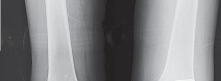

ما هو الانحراف التقوسي (Varus Deformity) في الركبة؟

الانحراف التقوسي، المعروف أيضًا بـ "تقوس الساقين" أو "الركبة المقوسة"، هو حالة تتميز بوجود زاوية غير طبيعية في مفصل الركبة، حيث تتجه الركبة نحو الخارج بينما تتجه الكاحلين نحو الداخل عند الوقوف معًا. هذا يعني أن الساقين تبدوان مقوستين إلى الخارج، مما يضع ضغطًا مفرطًا على الجزء الداخلي (الإنسي) من مفصل الركبة.

في الركبة الطبيعية، يمر خط وزن الجسم بشكل متساوٍ تقريبًا عبر مركز المفصل. أما في الركبة التقوسية، فإن هذا الخط ينحرف نحو الجانب الإنسي، مما يؤدي إلى:

- زيادة الضغط على الغضروف الإنسي: يتسبب هذا الضغط المستمر في تآكل الغضروف في الجزء الداخلي من الركبة بشكل أسرع بكثير من الجزء الخارجي.

- تضييق المسافة المفصلية الإنسية: مع تآكل الغضروف، تقل المسافة بين عظم الفخذ وعظم الساق في الجانب الداخلي، مما يزيد من الاحتكاك والألم.

- تلف الأنسجة الرخوة: يمكن أن يؤثر الضغط غير المتوازن على الأربطة والأنسجة المحيطة، مما يزيد من عدم الاستقرار.

يُعد الانحراف التقوسي مشكلة شائعة وقد يكون خلقيًا (موجودًا منذ الولادة)، ولكنه غالبًا ما يتطور بمرور الوقت نتيجة لخشونة الركبة المتقدمة، حيث يؤدي التآكل غير المتساوي للغضروف إلى تفاقم التشوه. تصحيح هذا الانحراف هو جوهر جراحة استبدال مفصل الركبة التقوسي، وهو ما يتقنه الأستاذ الدكتور محمد هطيف لضمان استقرار المفصل وطول عمره.